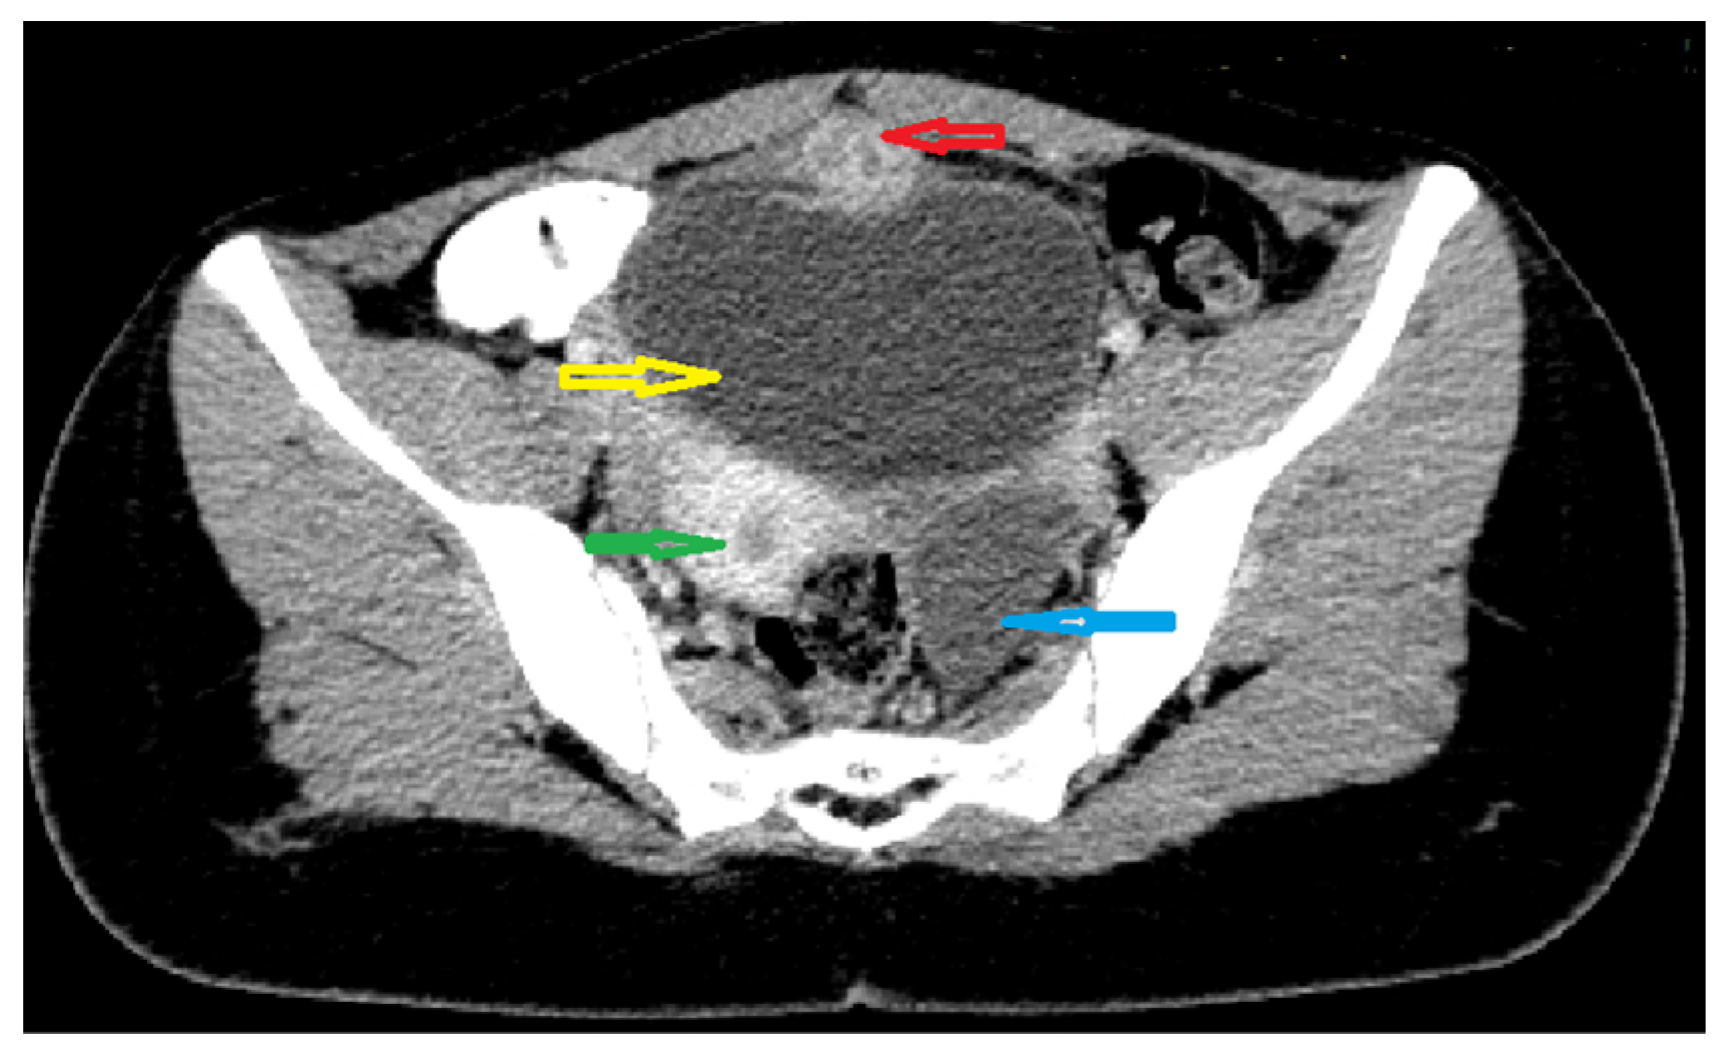

Because the radiologists requested additional investigations, an abdominal–pelvic CT scan with intravenous contrast was performed, adding an intense contrast capture in the periphery of the lesion with edema of the prevesical space (Figure 2 and Figure 3).

Figure 3. Axial CT scan of abdomen and pelvis with intravenous and oralcontrast: red arrow; supposed urachal cyst; yellow arrow: urinary bladder;green arrow: uterus; blue arrow: left ovarian cyst.